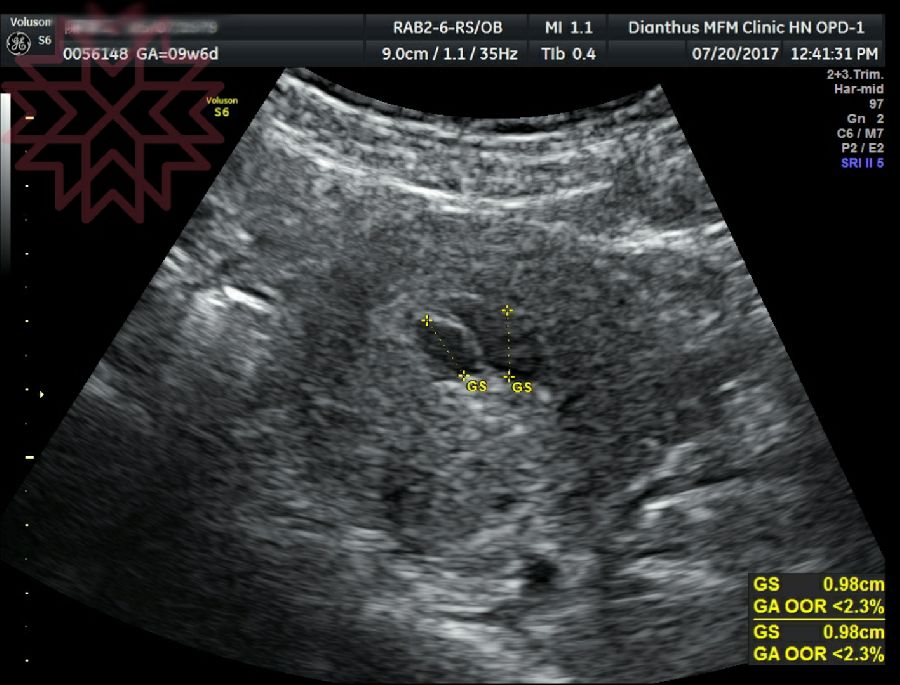

孕早期胚胎发育好不好 这几大关键指标给你答案

孕早期胚胎发育好不好 这几大关键指标给你答案 网易订阅

试管婴儿移植成功后 孕囊 胎心 胎芽多久能看见 知乎

孕5周 孕囊大小的标准值是多少呢 孕妈不妨自

孕早期b超能告诉我们什么 知乎

孕早期孕囊 胚芽 胎心完美三部曲 每日頭條

孕6周胎芽發育簡報 B超單上寫有這 四物 表明 坐胎 穩定 每日頭條